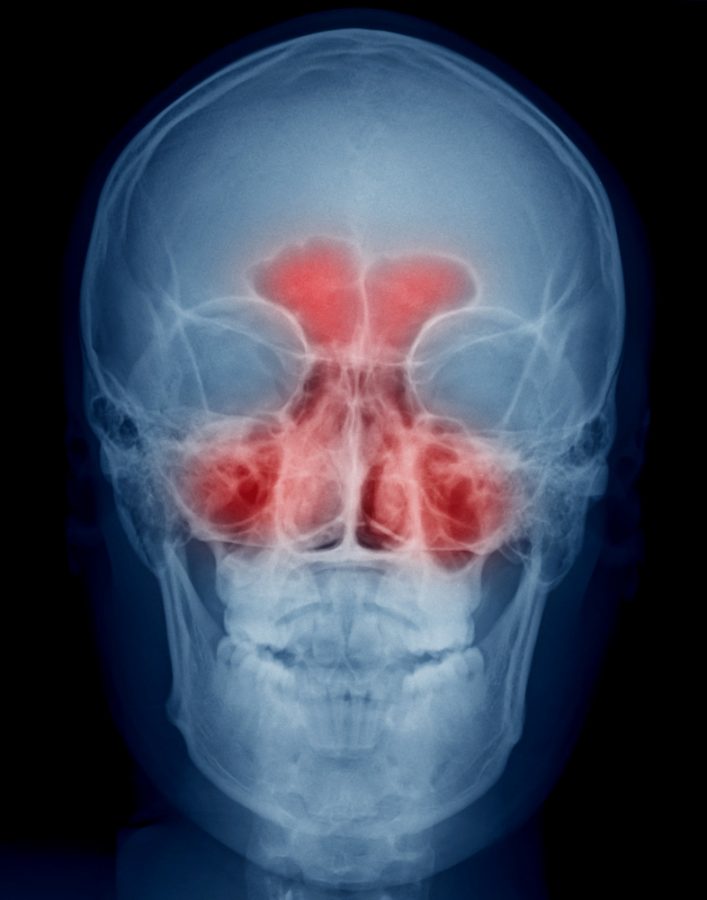

Рентгенография пазух носа – диагностический метод, который широко применяется практикующими врачами (обычно отоларингологами) для выявления заболеваний околоносовых пазух. Это весьма информативное исследование, но для получения достаточных данных о состоянии этих структур рентгенолог использует специальные укладки (положение исследуемой области по отношению к рентгеновскому лучу). Это связано с анатомо-топографическими особенностями пазух носа.

На основании данных, полученных по результатам рентгенографии, специалист может сделать вывод о наличии или отсутствии у больного синусита (гайморита, фронтита, этмоидита, сфеноидита), опухолевого процесса или другой патологии.

О состоянии пазух носа судят по интенсивности их затемнения. У здорового человека пневматизация пазух на рентгенологическом снимке должна соответствовать глазницам. При этом костные стенки, образующие пазухи, имеют четкие контуры. Значительным разнообразием строения отличаются клиновидные пазухи. Даже у одного и того же человека они могут быть асимметричными и различными по объему.

При наличии жидкости в пазухах на рентгенограмме появляется горизонтальный уровень. В некоторых случаях граница жидкости может приобретать изогнутый книзу контур. Обычно это происходит при нарушениях сообщения пазухи с носовой полостью.